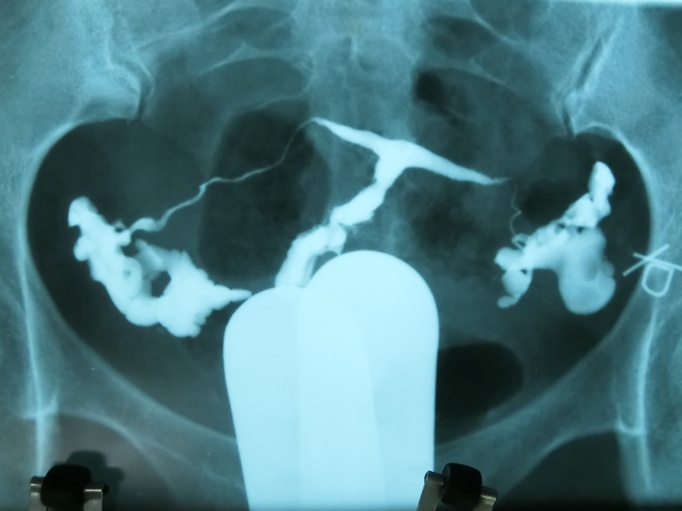

T型子宫有先天性和获得性之分,先天性是指患者胎儿期苯甲酸雌二醇(diethylstilbestrol,DES)宫内暴露或其他因素导致的先天畸形,成因为周边肌肉肥厚,致子宫腔近心端狭窄,中下段侧壁靠近,宫底可略内突,整个宫腔呈“ T ” 型外观(图1),宫体和宫颈长度比2:1。可导致不孕,反复流产,异位妊娠,宫颈机能不全,早产和围产儿死亡。获得性为宫腔粘连后、纤维瘢痕组织的形成,扭曲、塞满或闭锁宫腔,致其宫腔形态酷似“ T ”形,宫腔粘连的组织结构复杂,其边缘不规整,欠规则(图2),获得性T型子宫也与生殖道结核和子宫腺肌症相关,常导致不孕、复发性流产(recurrent pregnancy loss,RPL)和反复种植失败(repeated implantation failure,RIF)。

图2 获得性T型子宫HSG图片

患者张xx,31岁,孕8周钳刮人流,刮宫后闭经3年,于2006年9月12日 就诊我院。2005年9月6日外地宫检:宫腔狭窄呈试管状,行TCRA术,继服倍美丽+黄体酮 3 个月,未显效。2006年1月6日当地超声提示子宫下段长度约23mm,宫腔内膜未能显示,重度宫腔粘连致宫腔呈T型(图6)。2006年1月在当地行TCRA术,子宫穿孔,腹腔镜下修补。2006年9月12日我院宫检:宫颈内口粘连,进镜5cm,呈盲端。2007年12月17日静脉麻醉宫腔镜检查,见宫腔狭窄如缝隙,双输卵管开口未见,切除宫腔瘢痕组织,“人造” 宫腔,呈倒置三角形,宫深7cm。3日后出院,建议放弃手术治疗。术后仍无月经,间断雌孕激素治疗。一年后见少许月经,继服补佳乐3个月,自然妊娠。2009年3月26日孕38W+5,因脐带绕颈2周,剖宫产一健康女婴,4000+g,膜样胎盘。

图6 重度宫腔粘连致酷似T型子宫